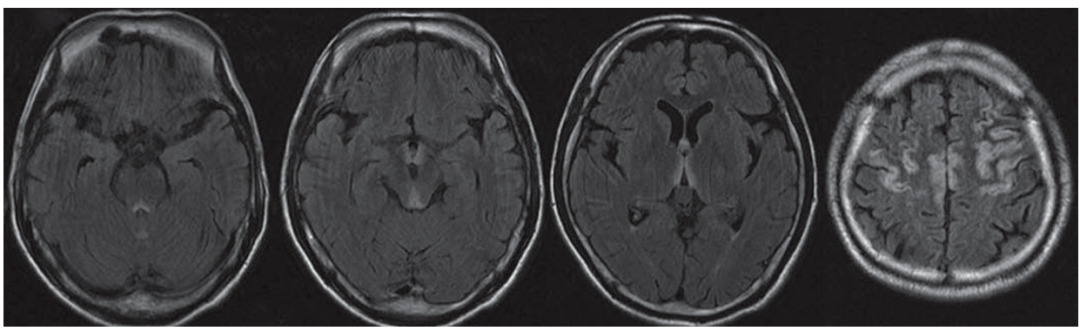

简称MBD,是一种罕见的以胼胝体脱髓鞘和坏死为主要病理特征的慢性酒精中毒相关性疾病。这种病的临床表现无特异性,急性起病者可出现严重的意识障碍和认知损害,常危及生命;慢性起病者主要表现为进行性痴呆。

急性期典型影像学表现为“三明治征”,即:矢状位上的病变主要位于胼胝体中层,上层和下层正常。以胼胝体全段受累更为常见。急性期后,胼胝体异常信号逐渐消退。

慢性期表现为胼胝体萎缩,伴局灶性长T1、T2信号,可能反映了进行性脱髓鞘、局灶性坏死和囊变。如果病变出现在胼胝体外,则以皮质下白质最为多见。

颅脑MRI矢状位FLAIR示胼胝体压部高信号(A)

DTI示同一部位胼胝体横向纤维受损(B)

DWI和ADC示胼胝体压部细胞毒性水肿(C、D)

颅脑MRI、DWI示:

双侧大脑半球皮层下白质、

胼胝体、双侧小脑中脚高信号